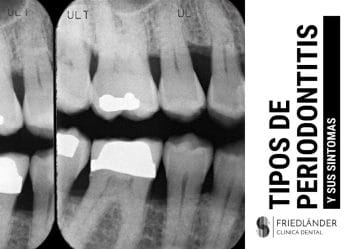

- Pérdida rápida de soporte óseo. Este síntoma normalmente se detecta a través de radiografías dentales.